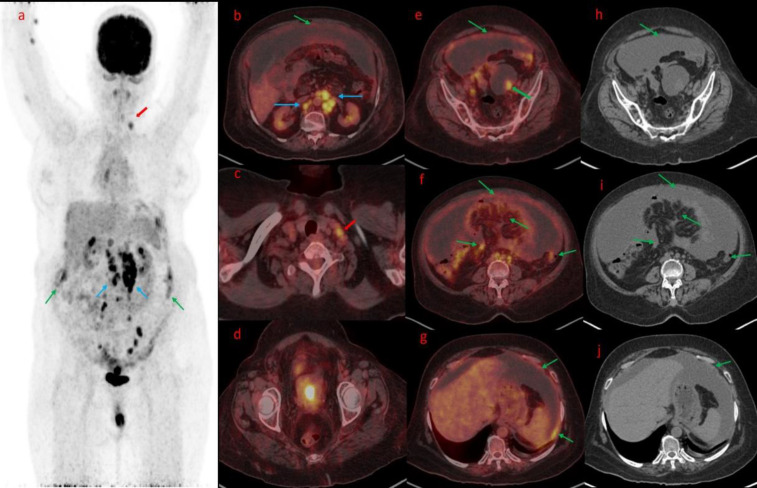

腹膜癌肿(PC)是癌细胞在腹膜中的扩散,是晚期胃肠道癌症和妇科癌症的一个重要问题。本病例系列包括 18F- 氟脱氧葡萄糖正电子发射断层扫描/CT(18F-FDG PET/CT)上 PC 的外观和模式。腹膜播散的主要来源是腹部或盆腔肿瘤的直接侵犯和远处肿瘤的转移扩散。准确的术前诊断和 PC 定量对确定适当的治疗方法起着至关重要的作用,尤其是在手术规划方面。术前评估采用了多种成像模式,如计算机断层扫描(CT)、磁共振成像(MRI)和 18F-FDG PET/CT。在这些方法中,18F-FDG PET/CT 显示了更好的解剖定位和病理结果性质的准确信息。本系列病例展示了四个病例,说明了 PC 在 FDG PET/CT 上的成像特点。FDG PET/CT 在诊断和评估 PC 方面发挥着重要作用,有助于 PC 的检测、分期和治疗计划。它在识别和描述病变以及在原发肿瘤位置不明的情况下检测原发肿瘤部位方面超越了传统的成像技术。此外,FDG PET/CT 还有助于评估治疗反应和监测疾病进展,为了解治疗效果和指导患者管理决策提供依据。

Peritoneal carcinomatosis (PC), the spread of cancer cells in the peritoneum, is a significant concern in advanced gastrointestinal and gynecological cancers. This case series includes findings on the appearance and pattern of PC on 18F-fluorodeoxyglucose positron emission tomography/CT (18F-FDG PET/CT). The primary sources of peritoneal dissemination are direct invasion from abdominal or pelvic tumors and metastatic spread from distant tumors. The accurate preoperative diagnosis and quantification of PC play a vital role in determining the appropriate treatment approach, with a particular emphasis on surgical planning. Several imaging modalities have been employed in preoperative evaluation, such as computed tomography (CT), magnetic resonance imaging (MRI), and 18F-FDG PET/CT. Among these modalities, 18F-FDG PET/CT has demonstrated improved anatomical localization and accurate information about the nature of pathological findings. The case series showcases four cases that illustrate the imaging characteristics of PC on FDG PET/CT. FDG PET/CT plays a vital role in diagnosing and assessing PC, aiding in its detection, staging, and treatment planning. It surpasses conventional imaging techniques in identifying and characterizing lesions and detecting the primary tumor site in cases where its location is unknown. Furthermore, FDG PET/CT additionally assists in evaluating treatment response and monitoring disease progression, providing insights into treatment effectiveness and guiding patient management decisions.